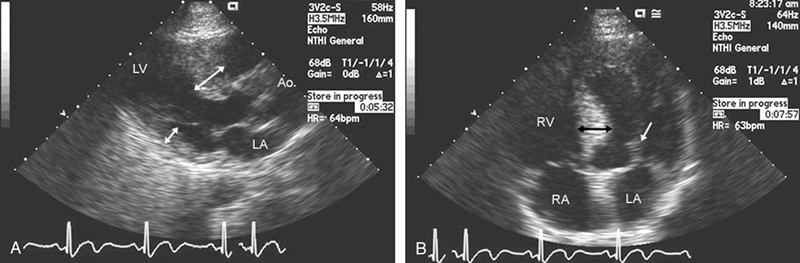

فحوصات تشخيصية لبعض امراض القلب والشرايين التاجية